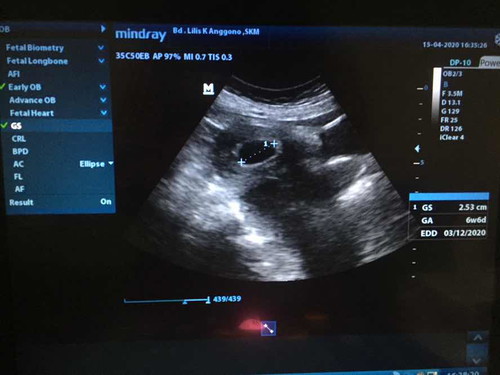

Kemarin saya usg ternyata usia kandungan memasuki 6weeks dan baru kelihatan kantungnya saja, apa ini wajar??

sama bun ni aku juga 6w6d baru kntung ya z mlah d vonis harus d kuret tp aku nya minta tunggu dulu boleh dok untung kata dokter ya boleh tunggu mpe 8weeks